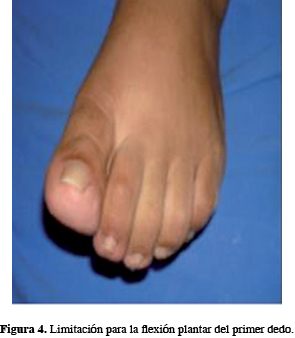

Primera cirugía (11 de mayo de 2011): Se somete la paciente a una primera cirugía en el Servicio de Artroscopía del Instituto Nacional de Rehabilitación, que consiste en artroscopía de tobillo izquierdo. Se visualiza por el portal posterior de la articulación subastragalina, que presenta abundante sinovial inflamada; se rasura, se localiza el os trigunum de 1 por 1 cm, aproximadamente, el cual se diseca y se extrae a través de los portales; se localiza el tendón del flexor del hallucis longus, el cual se observa inflamado; se decide realizar un peinado del mismo, siendo la evolución de mejoría parcial. Al mes presenta nuevamente los síntomas, con dolor intenso en el tobillo y la planta del pie en la cara medial, disestesias sobre el trayecto del tibial posterior, disminución de la extensión del primer dedo, de predominio matutino, lo cual imposibilita la marcha y agrava el cuadro, haciéndose el diagnóstico de síndrome del túnel del tarso por clínica (Figuras 3 y 4).

La paciente se encuentra actualmente sin dolor en el tobillo izquierdo, lo que le posibilita la marcha, con disestesias leves del primer dedo en la región plantar y movilidad limitada para su flexión.